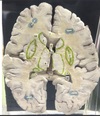

1. At what level through the cerebrum is this section taken? 2. Identify the specific structure labelled 1. 3. Identify the structure labelled 2. 4. Identify the structure labelled 5. 5. Identify the specific structure labelled 8. 6. Identify the structure labelled 10.

1. The level of interventricular foramen 2. Genu of Corpus Callosum 3. Septum Pellucidum 4. Column of Fornix 5. Spleenium of Corpus callosum 6 Crus of Fornix

56

1. Identify the specific structure labelled 3. 2. Identify one afferent fiber of this structure. 3. Identify one efferent fiber of this structure.

Caudate Nucleus Cortico striate, thalamo striate, nigro striate , Striato pallidal , Striato nigral

1. Identify the specific space labelled 4 2. Give its developmental origin.

Anterior horn of lateral Ventricle Central Canal of neural tube

1. Identify the structure labelled 6.

thalamus

1. Identify the structure labelled 7. 2. Give its subdivisions. 3. Give its afferent fibers. 4. Give its efferent fibers.

1. Lentiform Nucleus 2. Putamen, globus pallidus externas, globus pallidus internus 3. Corticostriatal, nigrastriatal 4. striatonigral, striatalpallidal

1. Identify the structure labelled 9. 2. Identify the structure labelled 11. 3. Identify the vessels lining the structure labelled 11.

1. Tail of caudate nucleus (goes to amygdala) 2. Insular cortex 3. short perforator branches from the superior division of the middle cerebral artery (MCA)

1. Identify the structure labelled 12 2. What type of meninges covers this structure? 3. What is the main function of this structure? 4. In which ventricular structures is this structure present? 5. In which ventricular structures is this structure absent?

1. Choroid Plexus 2. Pia Mater 3. Produces SF in ventricles of brain 4. Lateral 5. cerebral aqueduct, frontal horn of the lateral ventricle, [1] and occipital horn of the lateral ventricle

1. Identify the specific structure labelled 13. 2. What fibers can be found in this structure?

1. Posterior Limb of Internal Capsule 2. Corticospinal Fibres

1. Identify the specific structure labelled 14. 2. What fibers can be found in this structure?

1. Anterior Limb of internal capsule 2. Frontopontine, thalamocortical